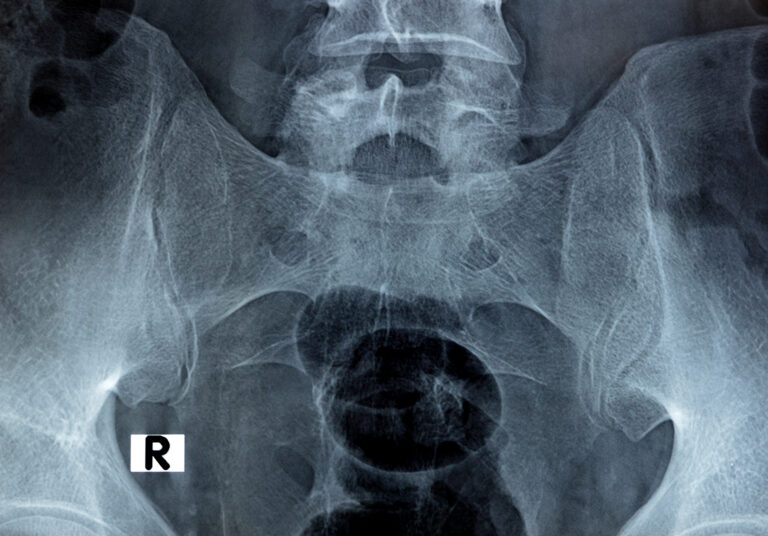

Back pain

Il dolore lombare è una condizione molto frequente. Può avere diverse cause, come problemi muscolari, articolari o discali, e spesso limita le attività quotidiane.